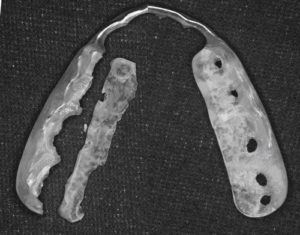

破壊防止用のマウスピースですが、人によっては作製して3ケ月で上のように真っ二つにマウスピースが割れてしまう方もいらっしゃいます。

それだけ噛む力がかかっている証拠です。男性では100キロちかくの噛む力がかかると言われています。

マウスピースが割れても折れても穴があいても修理することはいくらでもできます。

しかし、あなたの大事な歯が折れたり割れたり穴があいてしまった場合にはマウスピースのように簡単に修理というわけにはいかないのです。

マウスピースは歯の身代わりになってくれる存在

破折が根の奥から割れている場合には、最悪は抜歯ということになってしまいます。マウスピースはご自身の歯が割れる身代わりとなって割れてくれる存在です。